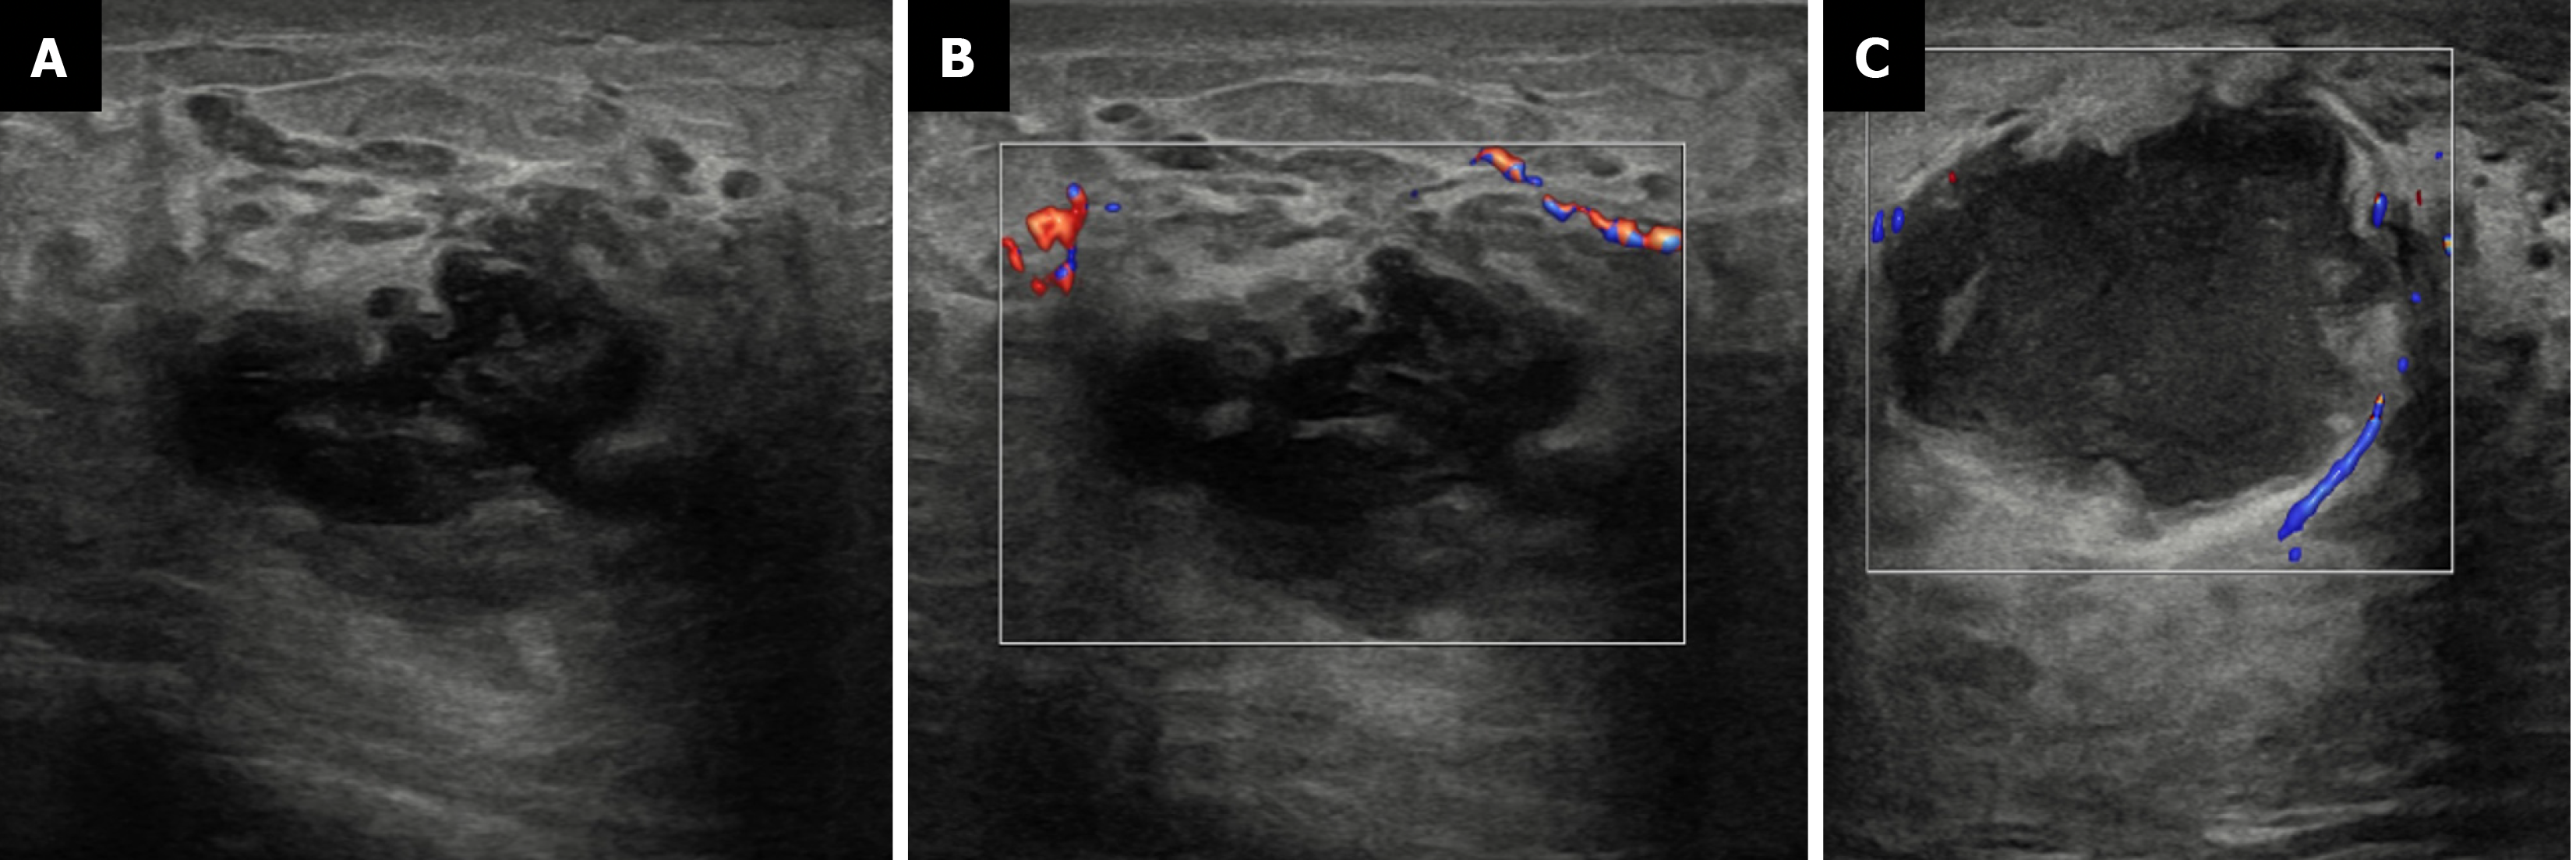

Figure 9 Mastitis with abscess in a 61-year-old diabetic male with a tender enlarged breast.

A: Ultrasound; B and C: Color Doppler images showing an irregular cystic collection with internal debris and peripheral vascularity. The surrounding fat appeared echogenic, suggesting inflammatory changes.